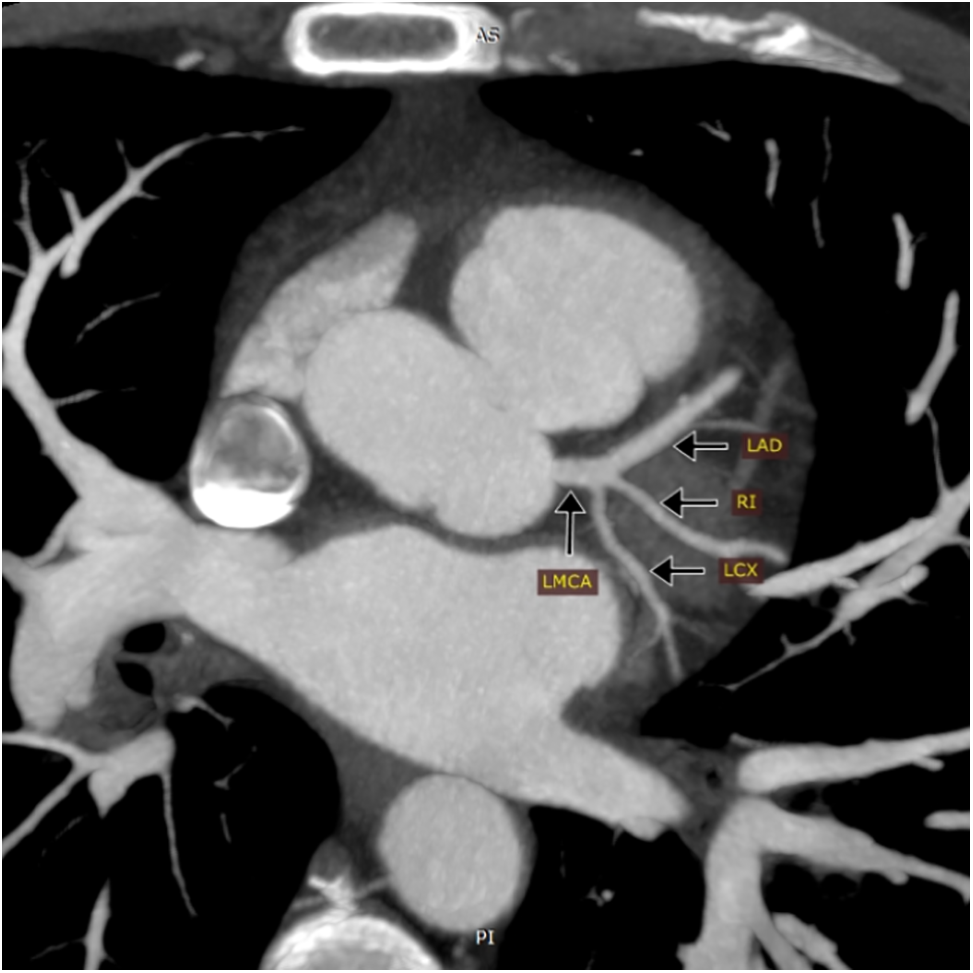

The evaluated coronary anatomical variations (CAVs) included short left main coronary artery (LMCA) of ≤5 mm, division pattern of LMCA with the presence of ramus intermedius (trifurcation and quadrifurcation), and non-right coronary dominance (Fig. 1).

Figure 1: Maximum intensity projection (MIP) of coronary CT angiography showing trifurcation of the left main coronary artery (LMCA) into the left anterior descending artery (LAD), Ramus intermedius artery (RI), and left circumflex artery (LCX)